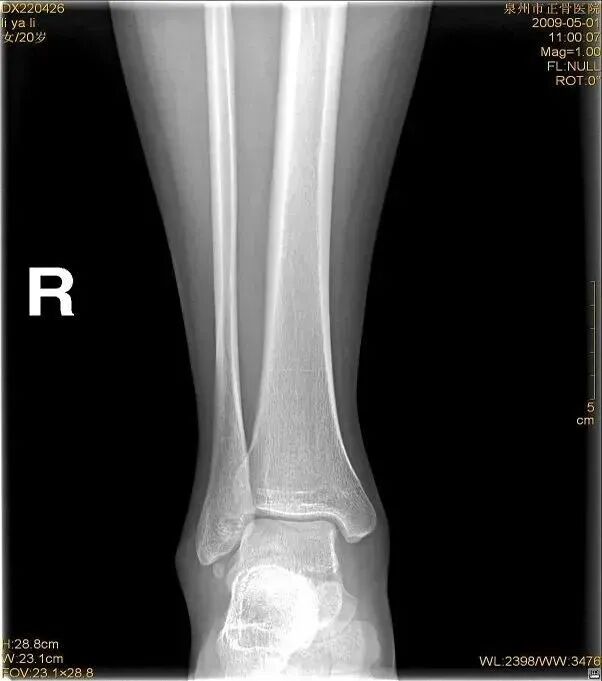

外旋位扭伤受伤时距骨受到外旋外力,或小腿内旋距骨受到相对外旋外力。随着外旋暴力增大下胫腓联合主要韧带断裂,下胫腓联合分离。严重的多合并外踝骨折或内侧韧带断裂。